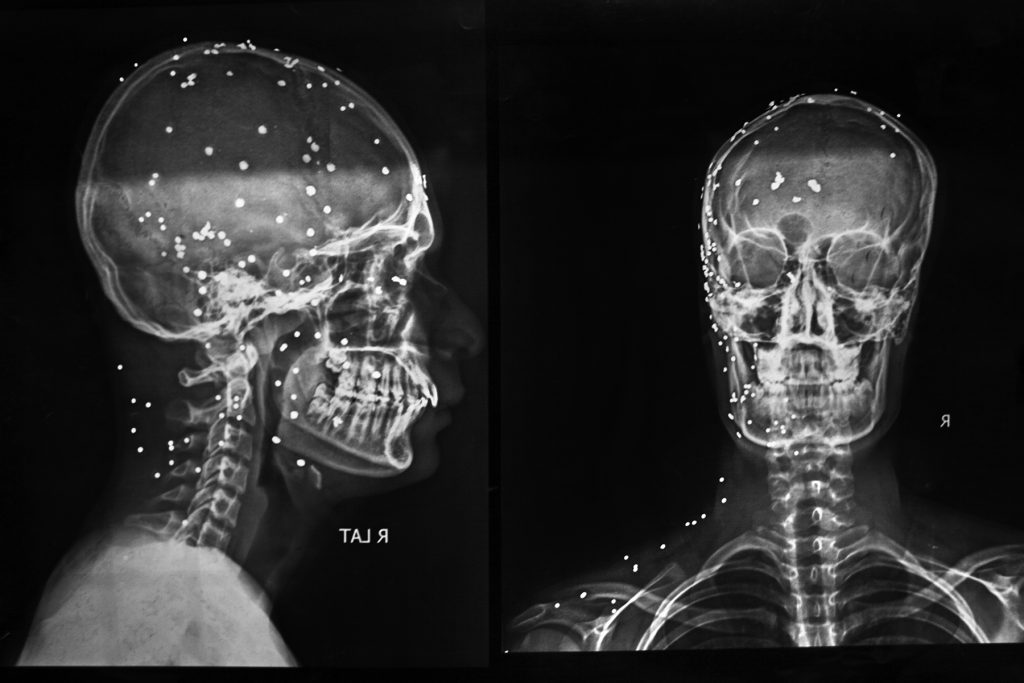

09 The New freedom fighters of Bangladesh 2024

Shahedul Islam Shakib, 22, a Feni Government College student, was brutally injured by police on August 5 in Feni. His left eye was destroyed and later removed, and his body contains over 450 pellets, with only seven removed; more than 150 remain in his head. Shakib, who participated in the movement daily from the start, was injured on three separate days, demonstrating his unwavering commitment despite his injuries.

On July 17 in Feni, Shahedul Islam Shakib’s left arm was broken by the ruling party’s student wing, the Chhatra League. After recovering, he rejoined protests on July 29. On August 4, his body was struck by numerous pellets. Despite his injuries, he returned on August 5, joining celebrations when Prime Minister Sheikh Hasina fled to India. During the ensuing chaos as protesters pursued police, Shakib was shot indiscriminately. He has been receiving treatment at Dhaka’s National Institute of Ophthalmology & Hospital (NIOH) for a year.

The image shows an X-ray of his head, with the dots representing the small bullets (pellets) embedded in his skull. This photo was taken on 21 March 2025, National Institute of Opthalmology & Hospital (NIOH) in Dhaka, Bangladesh.